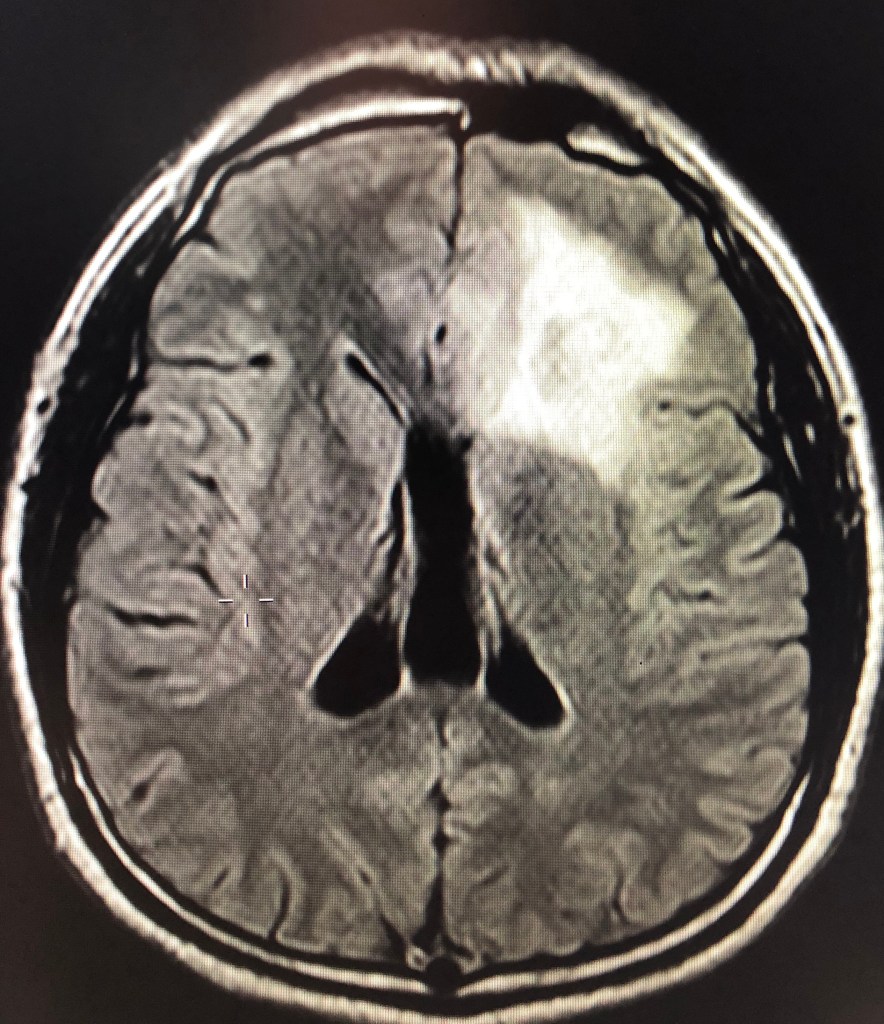

- เนื้องอกในสมอง(Brain Tumor)

- เนื้องอกชนิดกลีโอมา(Glioma)

- เนื้องอกชนิดร้ายแรง(Glioblastoma)

- มะเร็งแพร่กระจายมาที่สมอง(Brain metastasis)

- เนื้องอกในสมองที่อยู่ในโพรงน้ำเลี้ยงสมอง(Intraventricular tumor)

- เนื้องอกสมองชนิดอื่นๆ

- เส้นเลือดในสมองแตก(Intracerebral hemorrhage)

- เส้นเลือดผิดปกติในสมอง(AVM, Cavernoma)